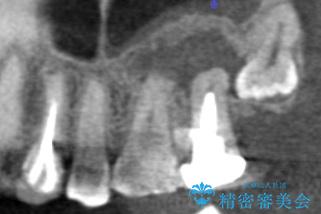

精査したところ、奥歯(左上67)の根尖部に位置した歯茎に瘻孔(膿の出口)ができており、CTを撮影し確認すると奥歯2本(左上67)の根尖病変は大きくつながっていました。

銀座しらゆり歯科の林院長による精密根管治療を受けて頂いたのち、メタルボンドクラウンによる補綴を行いました。